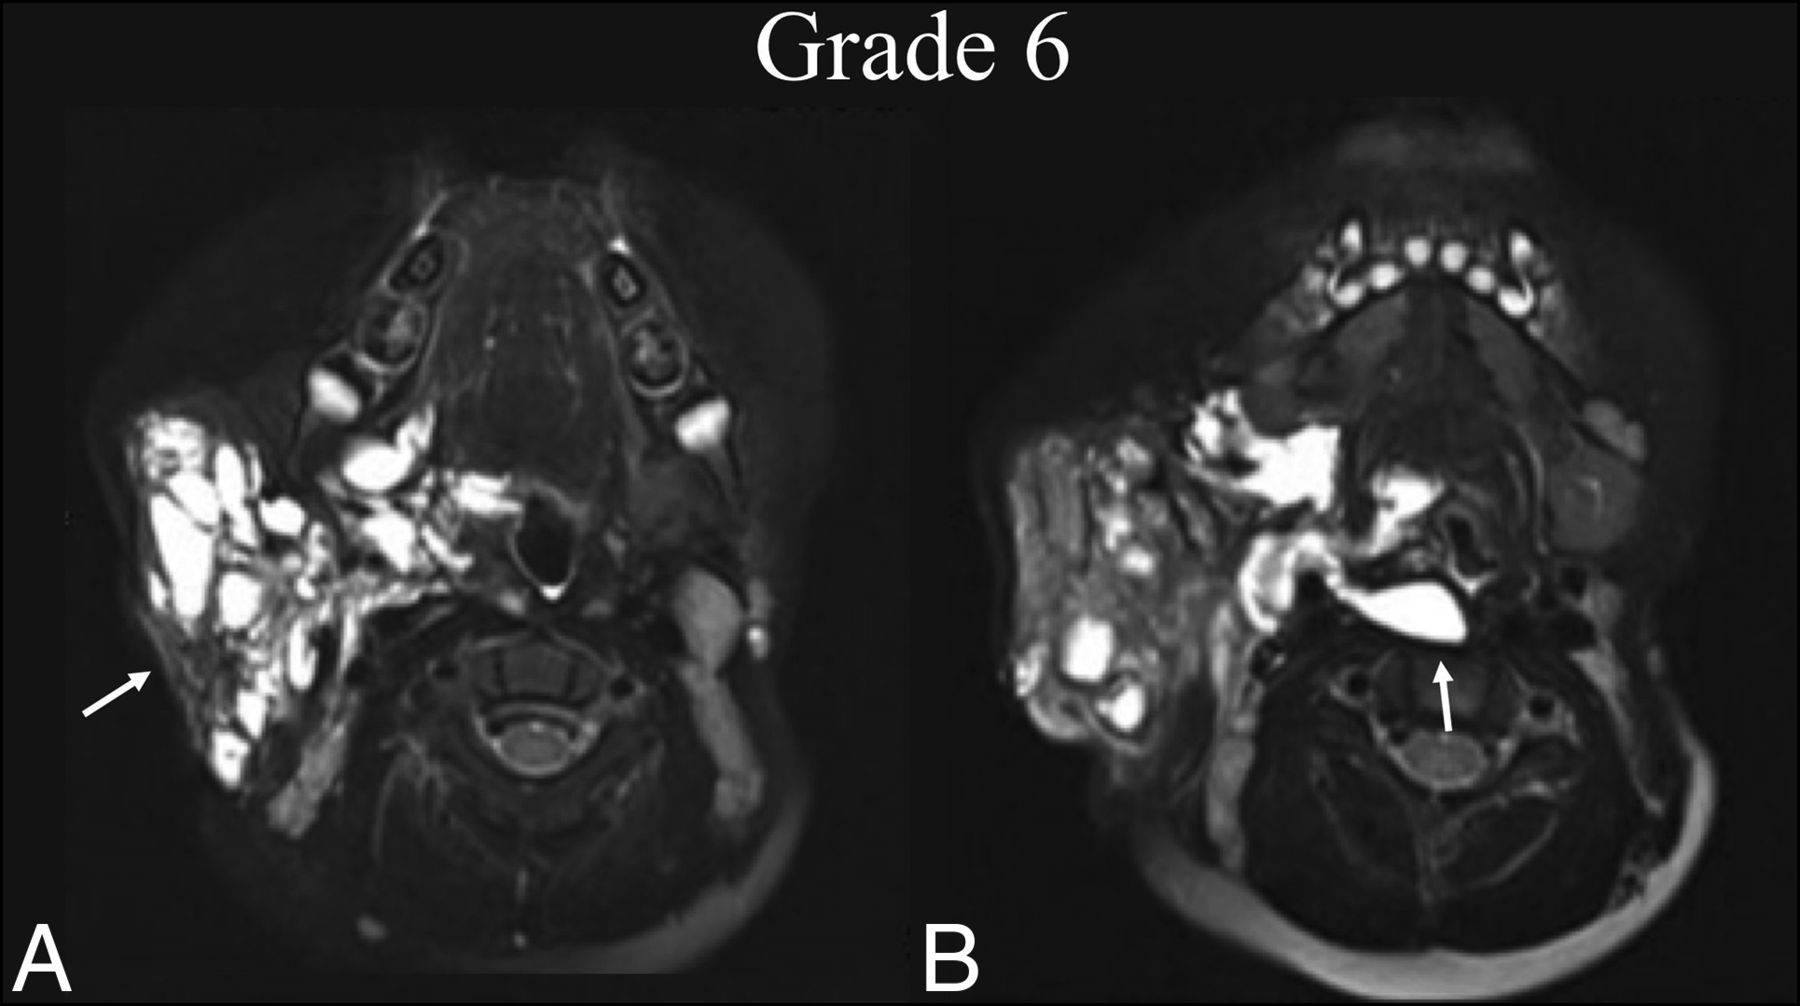

BDL grade 6 response. An 8-year-old boy with right facial prominence was found to have a de Serres stage II mixed macro-/microcystic LM. A, Preprocedural T2 fat-suppressed axial MR imaging at the level of the oropharynx shows trans-spatial involvement of the right neck extending from the right parotid and masticator spaces to the pharyngeal mucosal space (white arrow), sparing the retropharyngeal space. B, One year later, following 2 sclerotherapy treatments, T2 fat-suppressed axial MR imaging at the same level shows BDL grade 6 regression within the treatment bed and extension into the retropharyngeal space, which was previously uninvolved (white arrow).